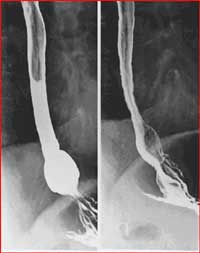

- Barium Swallow: evaluates the pharynx and esophagus including the swallowing mechanism. It includes conventional barium esophagram (barium swallow) and modified barium swallow (oral and pharyngeal function study).

Esophagram